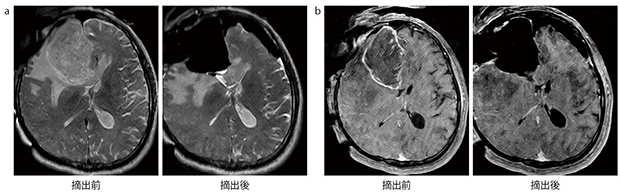

a:摘出前後の術中T2強調画像

b:摘出前後の術中造影T1強調画像